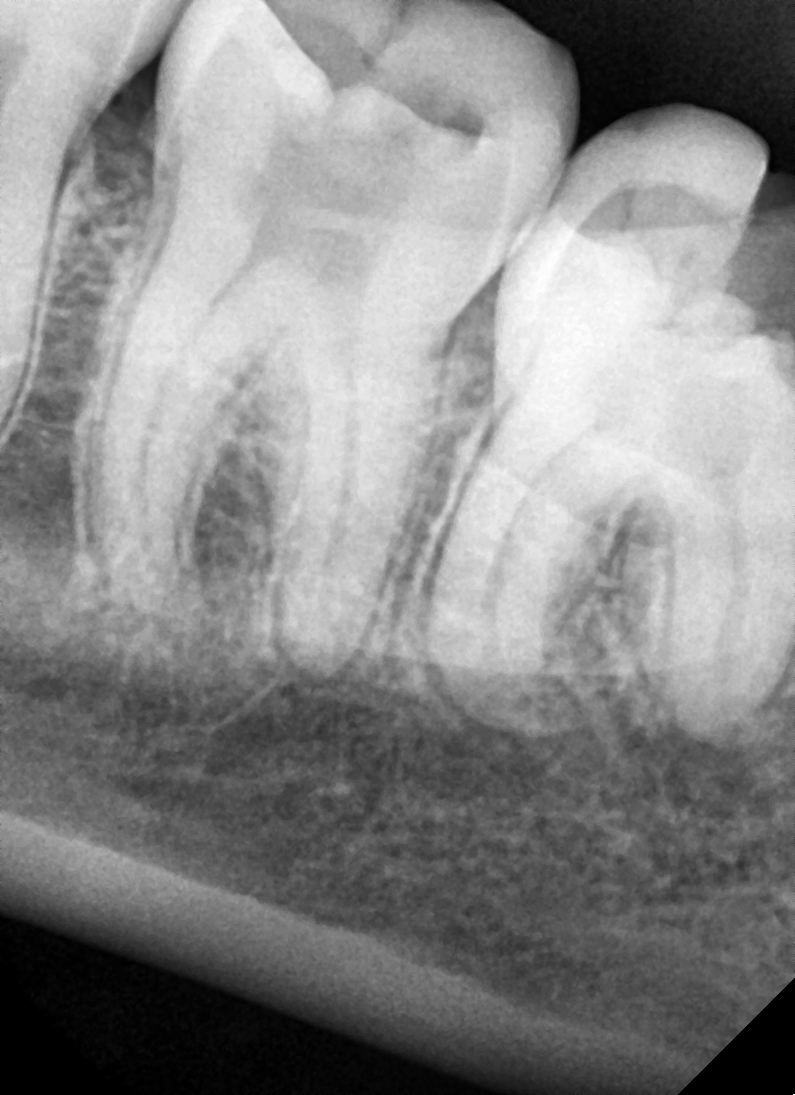

Mesioangular

After After

Before Before